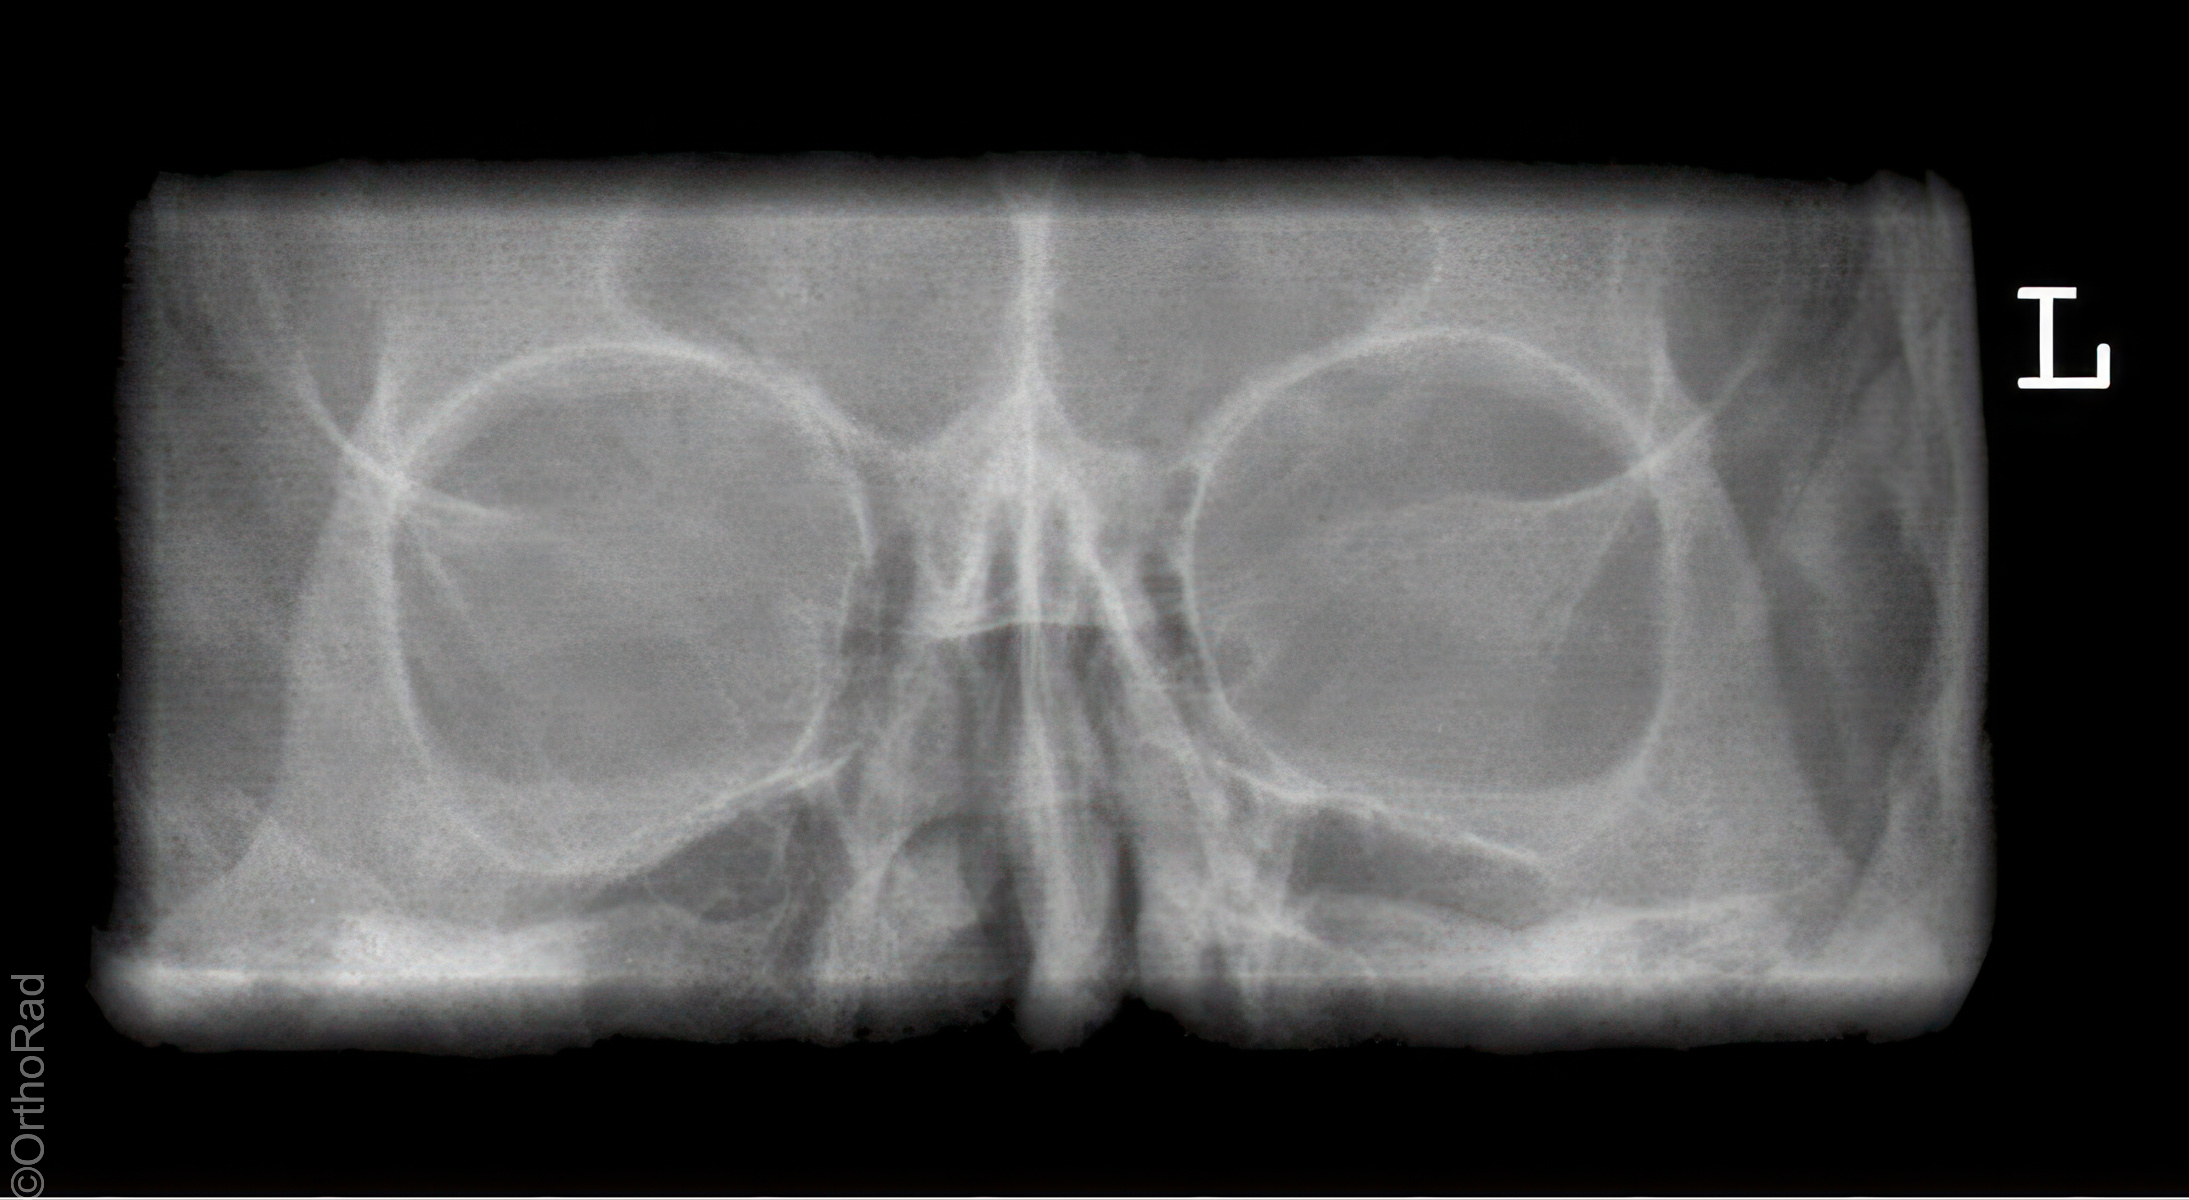

Orbita p.a.

Technik

• FDA: 1,15 m

• Ausgangsformat: Detektor oder 18/24 quer

• mit Raster

Lagerung

sitzend mit Gesicht zum Stativ

Hände festhaltend am Stativ

Nase liegt auf

Orbitadach und Orbitaboden stehen senkrecht zueinander

Zentralstrahl

Querstrahl: Augenwinkel

Längsstrahl: Medianebene

Einblendung

rechteckig, 1 QF über der Augenbraue,

seitlich: Hautgrenze

Qualitätskriterien

Symmetrische, runde (leicht vergrößerte) Orbitae. Überlagerungsfreie Darstellung der Augenhöhlen. Die Felsenbeine projizieren sich in die Kieferhöhle. Der Orbitaboden und der Orbitarand bilden eine Linie.